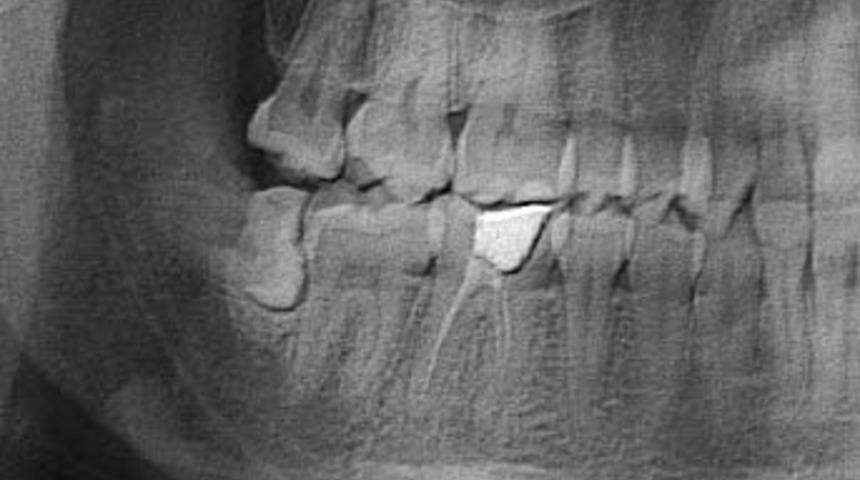

Eğer doğru pozisyonda sürerlerse ve çevre dokulara zarar vermiyorlarsa bu dişlerin çekilmesine gerek yoktur. Panoramik röntgen kontrolü sonucu tespit edilebilen ve çene kemiği içinde anormal pozisyonlu bir yirmi yaş dişinin ileride yol açacağı zararlar göz önüne alınarak çekimine karar verilebilir.

Çene kemiğindeki yer darlığı nedeniyle bu dişler çıkarlarken çene kemiğine ya da bir öndeki dişe takılabilirler.

Diş hekimi İbrahim Hepdarcan bunun nedenini insanoğlunun ve çene kemiğinin binlerce yıl içerisinde geçirmiş olduğu evrim sonucu olarak küçülmesi ve yirmi yaş dişlerinin küçük çene kemiği içerisinde yeterli yer bulamamasından kaynaklandığını söylemektedir.